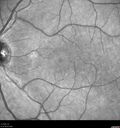

BRAO - plaques in vessels - GIF video of FA3 views78 year old female with vision loss for 1 week and old macular scar. Images show BRAO with plaques and FA shows occlusion.Oct 13, 2025

BRAO - plaques in vessels - GIF video of FA2 views78 year old female with vision loss for 1 week and old macular scar. Images show BRAO with plaques and FA shows occlusion.Oct 13, 2025